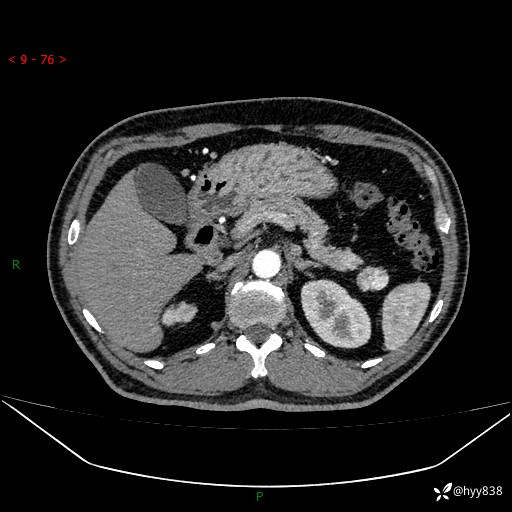

增强动脉期